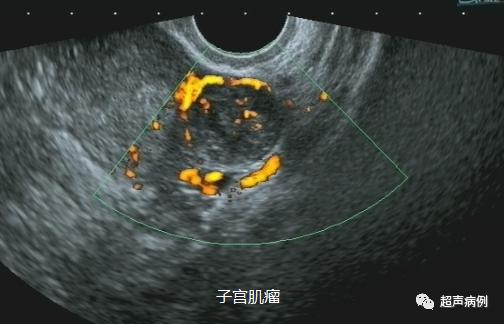

2、子宫病变的观察(如:子宫肌瘤、腺肌症、息肉、内膜癌等;